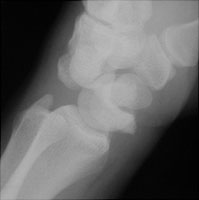

- Click on the image for a larger versionAPA radiograph of the wrist. This demonstrates the abnormal relationship between the scaphoid and lunate bones.

The perilunate dislocation results from a backwards fall on an extended hand which disrupts the scaphoid ligaments. The capitate is dorsally located relative to the lunate. The lunate bone maintains its normal relationship with the radius.